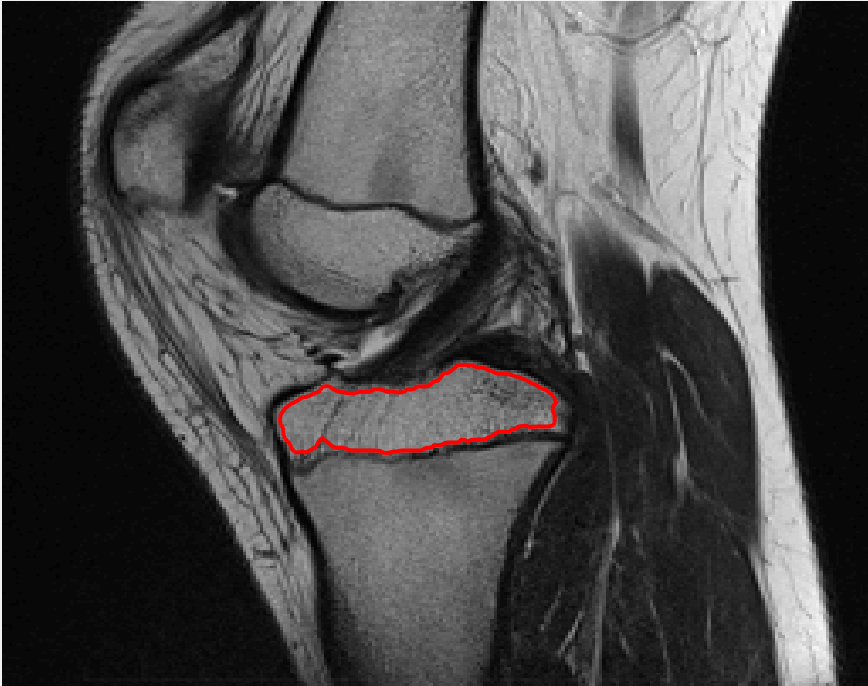

Refer to caption

(g) M7 λ=10,θ=1formulae-sequence𝜆10𝜃1\lambda=10,\theta=1.

Figure 11: Visual comparison of M1 – M7 results for Test Image 2. M1 segmented part of the object, M2 – M4 failed to segment the object, M5, M6 and M7 correctly segmented the object.